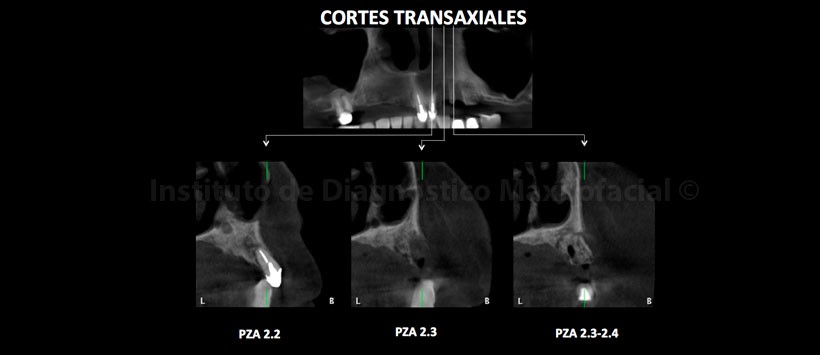

A la evaluación de la tomografía volumétrica (CBCT) en los cortes axiales (Figura 2, 3), coronales (Figura 4,5), transaxiales (Figura 6,7) y tangenciales (Figura 8), se aprecia proceso osteolítico de límites mal definidos, bordes difusos, localizado a nivel del maxilar superior del lado izquierdo, que se extiende en sentido mesio-distal desde la pieza 2.2 hacia los lechos alveolares de las piezas 2.3 y 2.4 y en sentido cefálico-caudal de la címa de reborde alveolar hasta el piso del seno maxilar a nivel de la zona de pieza 2.5. Se aprecia, presencia de secuestros óseos y reacción periostal en la tabla ósea vestibular y en zona del piso del seno maxilar.